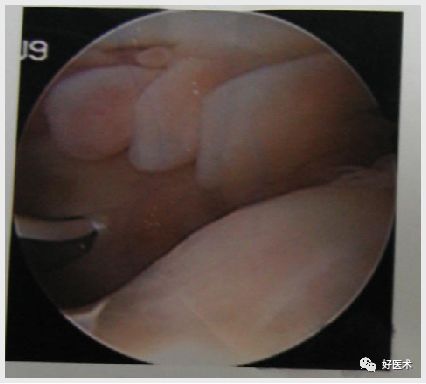

关节镜检查

受累关节均滑膜肥厚、充血、水肿、部分滑膜破裂在关节内呈纵形裂开、 肥厚 ,并有绒毛和皱襞形成;绒毛呈暗红色或棕黄色,长者如珊瑚状,短者增殖融合呈结节样变,直径1~3cm不等,亦呈红棕色或黄褐色,中老年人伴有不同程度软骨退变

关节镜下检查同时可以取滑膜组织进行病理检查